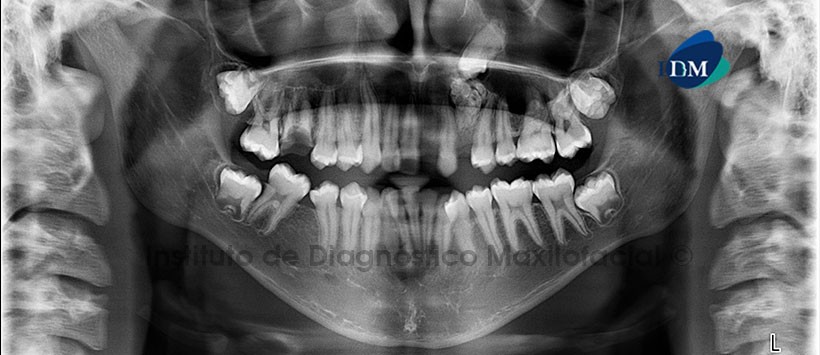

Paciente masculino de 16 años de edad es referido al Instituto de Diagnóstico Maxilofacial (IDM) para su evaluación y diagnóstico.

A la evaluación de la radiografía Panorámica (Figura 1) se apreció la impactación de la pieza 23 contra una lesión radiopaca de densidad dentaria ubicada entre las piezas 22 y 24, de límites definidos, sugerente de Odontoma compuesto. Además, se evidenció una tenue imagen radiolúcida en el tercio cervical de pieza 23 de contorno irregular. Como hallazgo radiográfico se evidenció la bifurcación bilateral del conducto dentario inferior. A la evaluación de la tomografía computarizada Cone beam mediante cortes axiales, coronales, sagitales (Figura 2) y transaxiales (Figura 3), se evidenció a la pieza 23 impactada, en posición mesioangular, con su corona orientada hacia la tabla ósea vestibular, dilaceración radicular transversal en el tercio apical con orientación hacia la pared lateral de fosa nasal del lado izquierdo e imagen hipodensa en el tercio cervical radicular, compatible con reabsorción cervical invasiva.

Se encontró, además, una imagen hiperdensa ubicada entre las piezas 22 y 24, conformada por múltiples dentículos y rodeada por un halo hipodenso, de limites definidos y bordes corticalizados, que se extiende desde la tabla ósea vestibular hasta la tabla ósea palatina. Signos tomográficos de odontoma compuesto.